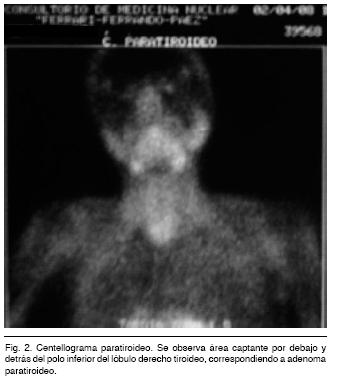

Tomografía cuello, tórax, abdomen (Figura 1): debajo de la tiroides y detrás de la tráquea y del esófago, al que desplaza, se observa una formación ovoidea, sólida, captante, de bordes bien definidos de 25 x 30 mm, que puede corresponder a un adenoma paratiroideo. Resto del estudio normal.

Centellograma paratiroideo (Figura 2): área captante por debajo y detrás del polo inferior del lóbulo derecho tiroideo que sugiere un adenoma paratiroideo.